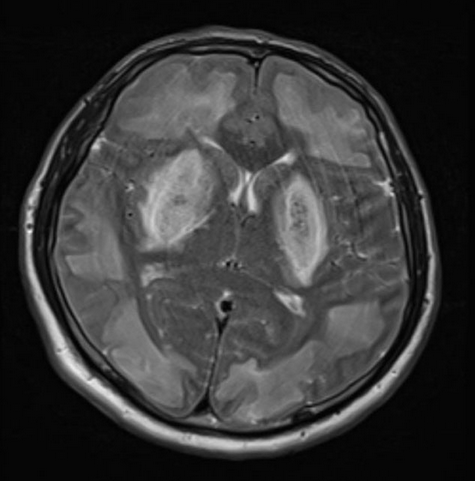

Em casos graves, pode ocorrer acidose metabólica importante, convulsões, coma e choque. Exames podem mostrar gap osmolar elevado (precoce) seguido de ânion gap alto. Achados neurorradiológicos típicos incluem lesões dos gânglios da base (putâmen).

- Camurcuoglu E, Halefoglu AM. CT and MR Imaging Findings in Methanol Intoxication Manifesting with BI Lateral Severe Basal Ganglia and Cerebral Involvement. J Belg Soc Radiol. 2022 Jul 6;106(1):66. doi: 10.5334/jbsr.2836. PMID: 35859917; PMCID: PMC9267022.